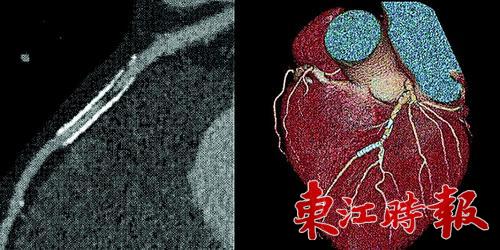

但是宝石能谱CT,却可以不受金属影响成影。不要小看这个功能,它带来的却是多种多样的CT新应用。惠州市第三人民医院医学影像科主任医师崔冰告诉记者,有的冠心病患者曾植入过支架,有的骨头受损伤的患者,身体内植入了钢钉,对面这些类型的患者,由于身体内有金属,再想通过常规CT来观察是不太可能了,而磁共振也无法很好的解决这一问题。过去,医生们只能用最为传统的方法,了解病人恢复是否理想来判断内部情况。现在使用宝石能谱CT,就可以通过成影直接看到患者植入钢钉的部位,如果出现问题,医生能够更加及时地发现,并对患者加以治疗。

“有一位60岁的患者,不愿开刀,就接受了宝石能谱CT检测。”崔冰称这位男性患者自称胸闷,伴有其它病史,对插管较为抵触。经过宝石能谱CT检测,医生在该患者的动脉里发现血栓已有部分钙化,并有管腔狭窄。“新血栓可用药物控制和溶栓,老血栓只能用支架撑开血管了。”崔冰表示,常规CT只能显示血栓,但是宝石能谱CT可以反映出新、老血栓,根据新旧的不同,采取的治疗方法也不同。如今该患者的病很快就得到了确诊,正在进行下一步的治疗。